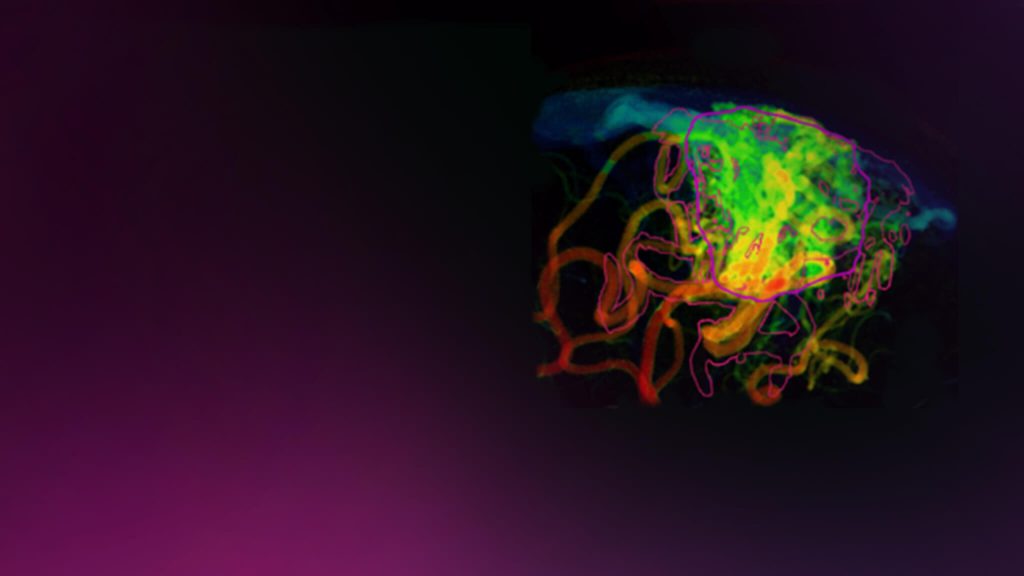

Çoklu Beyin Metastazı

Kraniyal Fonksiyon

Kraniyal Endikasyonlar